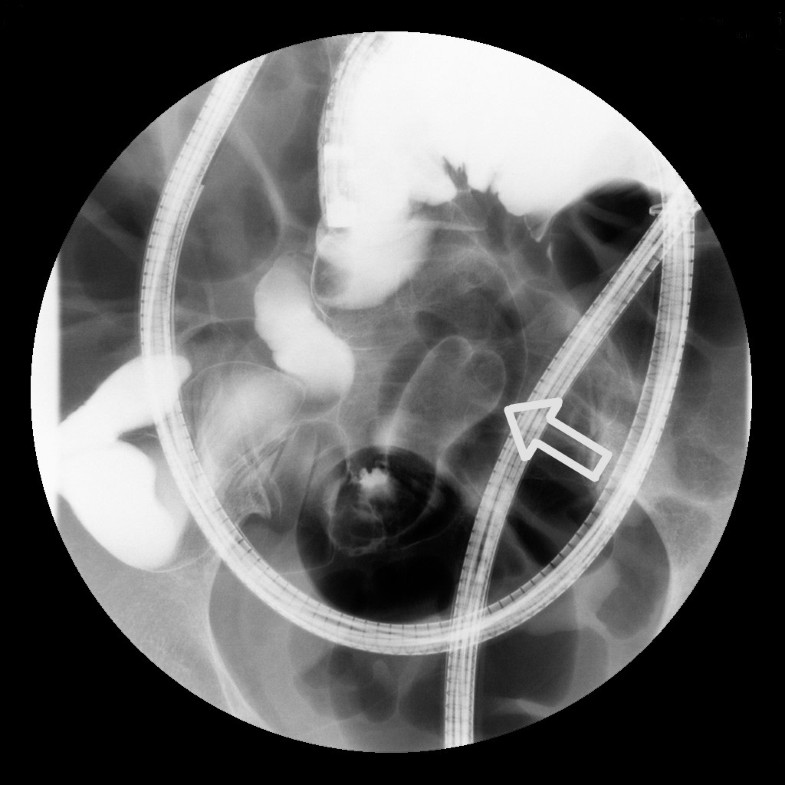

(PDF) Capsule endoscopy with retention of 4 years A case report Endoscopy Journal Case Report digestive endoscopy is a journal for promptly presenting research that offers significant contributions to the rapidly advancing field. A report of two cases jun ho. Endoscopy Journal Case Report.

(PDF) Journal of Clinical Case Reports Laparoscopic Removal of Retained Capsule Endoscopy due to Endoscopy Journal Case Report digestive endoscopy is a journal for promptly presenting research that offers significant contributions to the rapidly advancing field. A report of two cases jun ho. Endoscopy Journal Case Report.